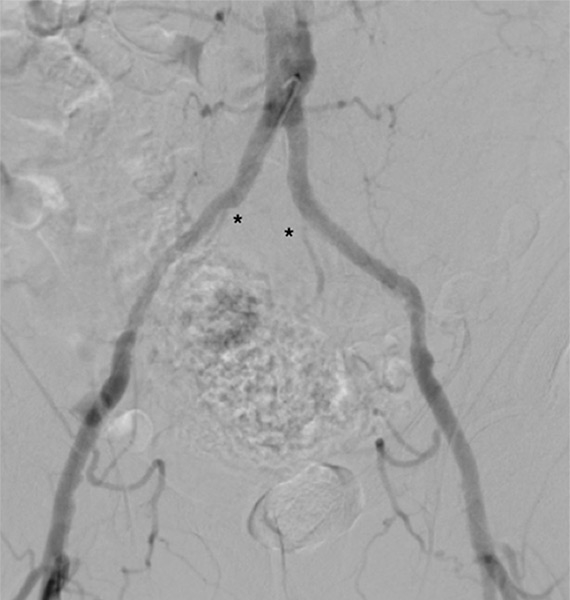

Figure 3

Sub-total occlusion of both hypogastric arteries (*) in a patient with cardiovascular risk factors and erectile dysfunction.

Endovascular therapy for obstructions of the common iliac and hypogastric arteries has traditionally been performed for many years. Figures 3 and 4 show angiograms of the pelvic arteries of a 62-year-old architect with erectile dysfunction. He had undergone aorto-coronary bypass grafting 3 years previously and, based on duplex ultrasound, an arterial inflow obstruction had been diagnosed. On intra-arterial angiography, a high-grade obstruction of both hypogastric arteries was diagnosed (fig. 3), both of which have been stented using drug-eluting stents (fig. 4). Erectile dysfunction in this patient was significantly improved during follow-up.